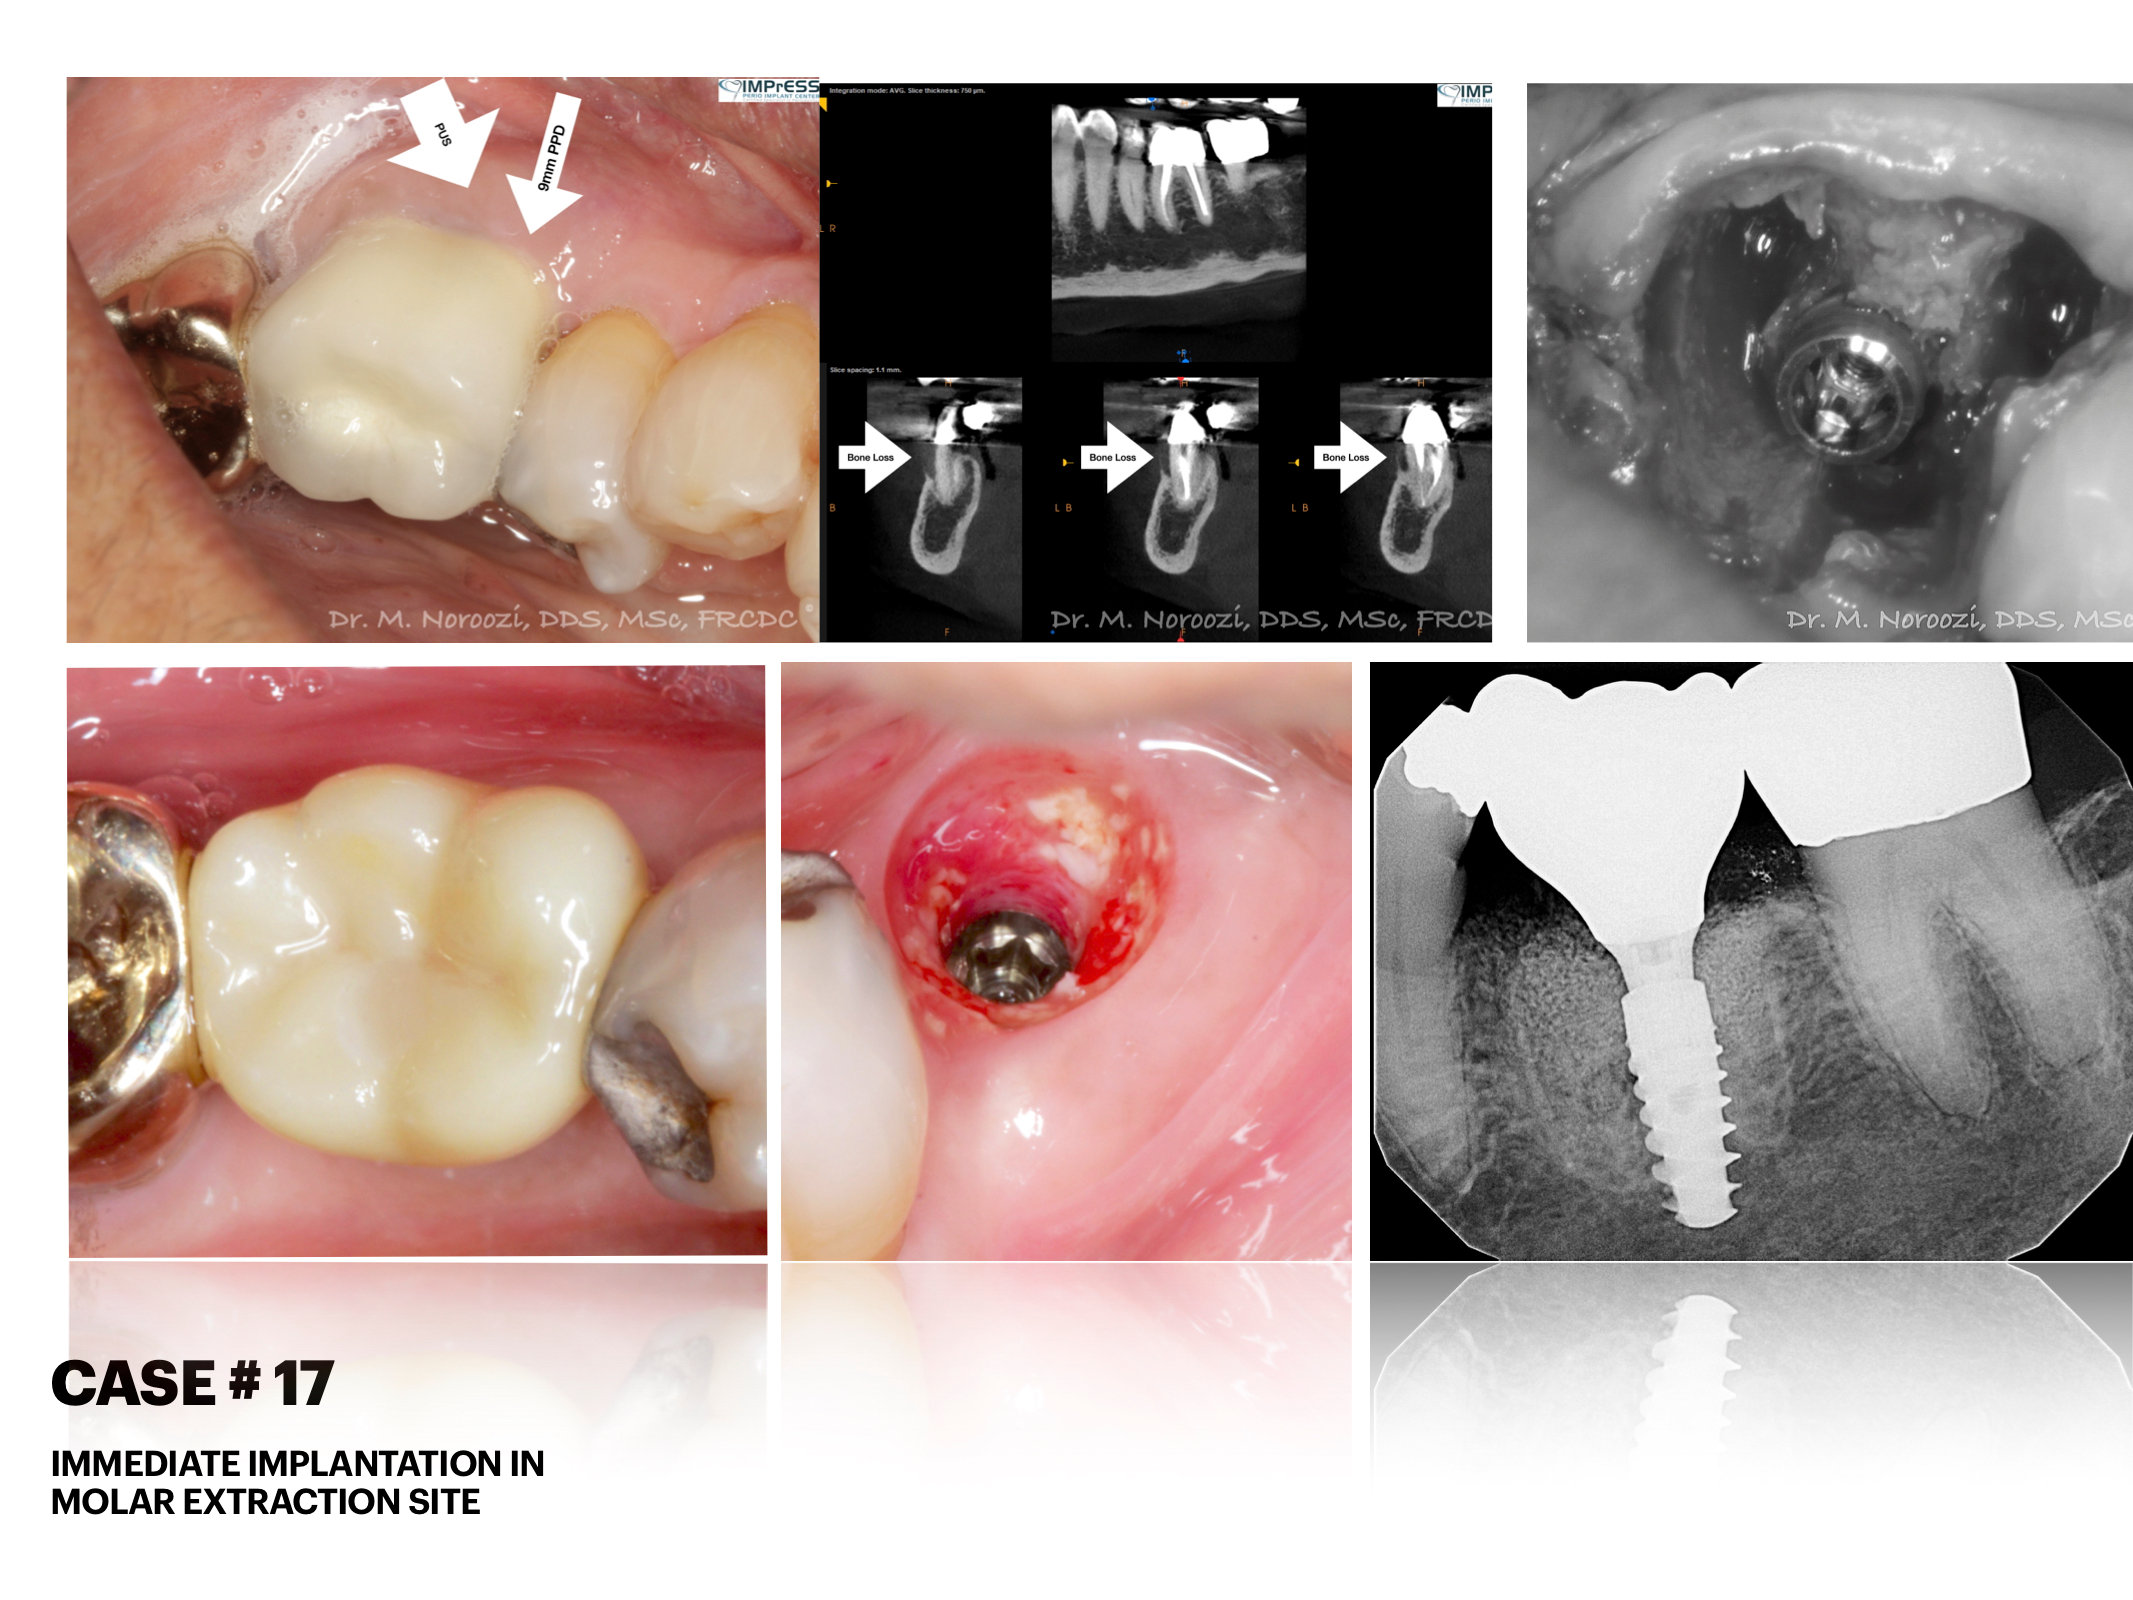

Before & Afters of Dental Implant Patients

Complete Dental Implant Cases Gallery

Surgical advances with SAME-DAY IMPLANTS in Vancouver BC

Using the most recent advances in dental implant technology, Dr. Noroozi is able to place single stage implants. These implants do not require a second procedure to uncover them but may require a minimum of six weeks of healing time before artificial teeth are placed. There are even situations where the implant can be placed at the same time as the tooth extraction and the artificial tooth can be inserted immediately following the implant placement – further minimizing your number of surgical procedures.

General Disclaimer: The results in the photographs are examples only and do not imply any certainty of the result of a procedure, and all outcomes are subject to the circumstances of the individual patient.